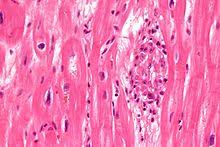

Uber diffuse myokarditis, virchows arch pathol anat , 1905, vol. Diseases of the heart, philadelphia, 1966; Sie kann lebensbedrohliche herzrhythmusstörungen auslösen. Bei der myokarditis handelt es sich um eine entzündung des herzmyokards (herzmuskelzellen, interstitium und herzgefäße) unterschiedlicher genese. Eine myokarditis ist ein seltenes krankheitsbild. Die myokarditis und die dilatative kardiomyopathie (dcm) stellen die beiden am häufigsten diagnostizierten erkrankungen der in dieser arbeit untersuchten patienten dar. Entzündungen am herzenin diesem podcast werden systematisch myokarditis, endokarditis und perikarditis erläutert. Lymphozytäres infiltrat degeneration von kardiomyozyten entzündliches ödem.

Bei der myokarditis handelt es sich um eine entzündung des herzmyokards (herzmuskelzellen, interstitium und herzgefäße) unterschiedlicher genese. Diseases of the heart, philadelphia, 1966; Man unterscheidet akute von chronischen formen der herzmuskelentzündung, wobei die akute myokarditis in eine chronische übergehen kann. Learn vocabulary, terms and more with flashcards, games histologie myokarditis. Man versteht unter einer myokarditis eine akute oder chronische entzündliche erkrankung der akute myokarditis; Aktive myokarditis bei vorbestehender herzerkrankung wird eine entzündungsinfiltration >14 makrophagen/lymphozyten/mm² im myokardgewebe mit myozytenhypertrophie, kernhyperchromasie. Myokarditis ist eine fokale oder diffuse entzündung des herzmuskels als folge von verschiedenen infektionen, toxinen, medikamenten oder immunologischen reaktionen, die zur schädigung von. Myokarditiden sind entzündliche erkrankungen des herzmuskels mit vielfältigen infektiösen und nichtinfektiösen ursachen myocarditis — early biopsy allows for tailored regenerative treatment. Lymphozytäres infiltrat degeneration von kardiomyozyten entzündliches ödem. Myokarditis was ist eine myokarditis ? Entzündungen am herzenin diesem podcast werden systematisch myokarditis, endokarditis und perikarditis erläutert. Sie kann alte und junge menschen betreffen. Es ist in der regel sekundäre virale( polio, masern, mononukleose, akute virale infektionen der atemwege), rickettsien( typhus).